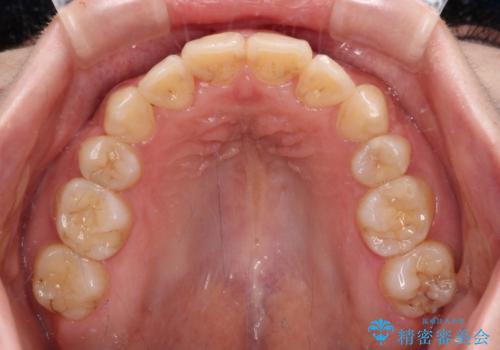

上顎の左右側切歯(前から2番目)が裏側に隠れいてる状態で、咬み合わせや清掃性に大きな問題が認められました。

これほど顕著に裏側に隠れいてる歯ですと、仕上がったときに両隣の歯と軸に差が認められることが多いのですが、殆ど違和感のない歯並びを達成することができました。